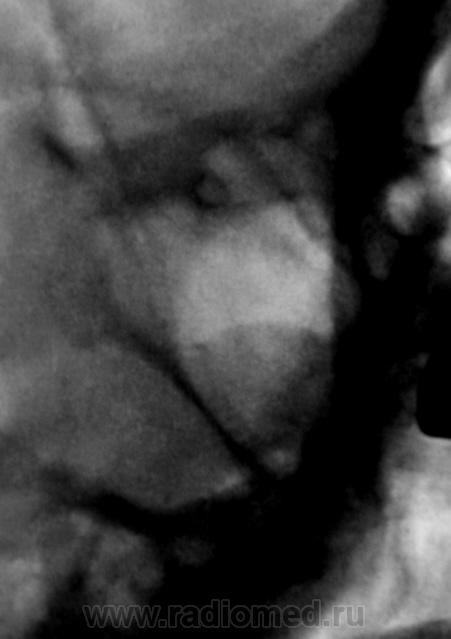

ну киста же прилежит к стенке пазухи, она однородная, а тут какой то участок просветления под ней. А что известно точно что это?

Да, и участок просветления под ней, да и "тень", от пазухи, весьма не скоромно распространяется латеральнее.

ага))))))))снаружи может что то наслаивается!

Нужна одна боковая линейная томограмма через середину правой верхнечелюстной пазухи.

1. Хорошо, не будем утверждать, что это киста.

2. Скиалогически имеем ОДНУ однородную тень с округлым контуром, ПЛАВНО (без острого угла) переходящую на латеральную стенку.

3. Утверждение о выходе ЗА ПРЕДЕЛЫ пазухи, как по мне, не имеет под собой достаточной аргументации.

4. ПРОСВЕТЛЕНИЕ под тенью есть и с противоположной стороны, хоть и выражено в меньшей степени (вспомните о симптоме Рейнберга).